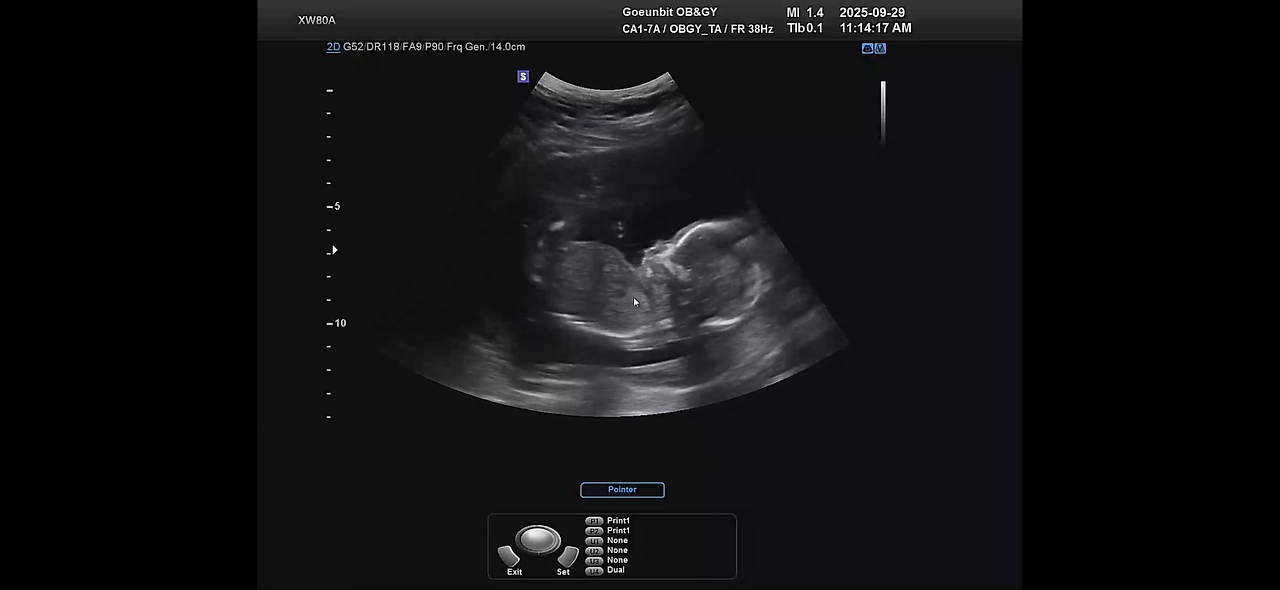

긴 대기 끝에 내 차례가 되었다.

초음파 화면이 켜지는 순간,

익숙한 ‘두근두근’ 소리가 들려왔다.

“아기 아주 잘 크고 있어요. 걱정 안 하셔도 됩니다.”

의사 선생님의 담담한 말투에

온몸의 긴장이 한꺼번에 풀렸다.

작은 화면 속에서 꼬물거리는 손가락,

움직이는 발끝.

그 모습을 보는 순간,

2주 전의 모든 걱정이 눈 녹듯 사라졌다.

KakaoTalk_20251031_113117637.png 16주 오복이